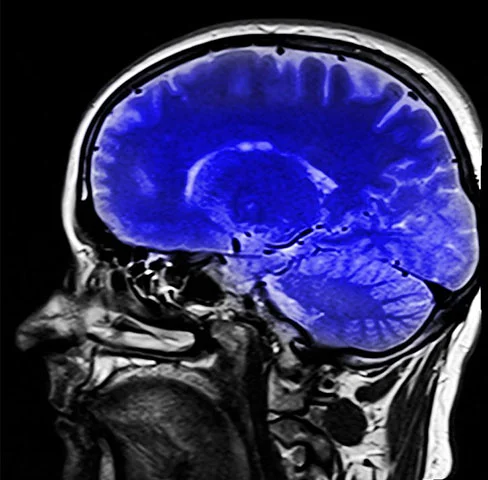

Pesquisa alerta: remédios para dormir podem aumentar risco de demência